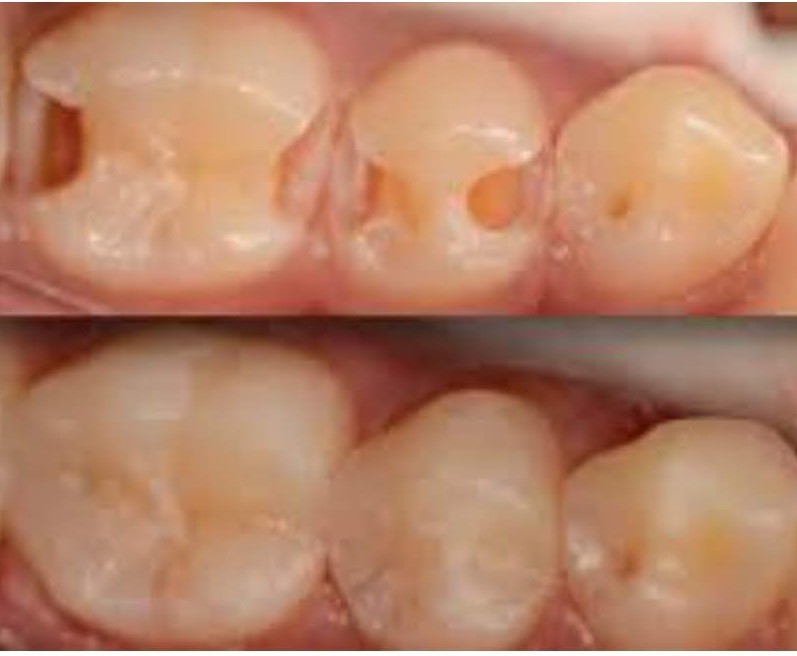

Реставративната стоматологија, пак, се надоврзува како уметност на враќање. Со користење на најсовремени материјали и технологии, се реконструираат оштетените или изгубените заби – без компромис во однос на природниот изглед, функцијата или удобноста. Без разлика дали станува збор за пломби, инлеи, коронки, мостови или импланти, секој реставративен зафат е прецизно дизајниран да се вклопи во хармонијата на вашата насмевка.